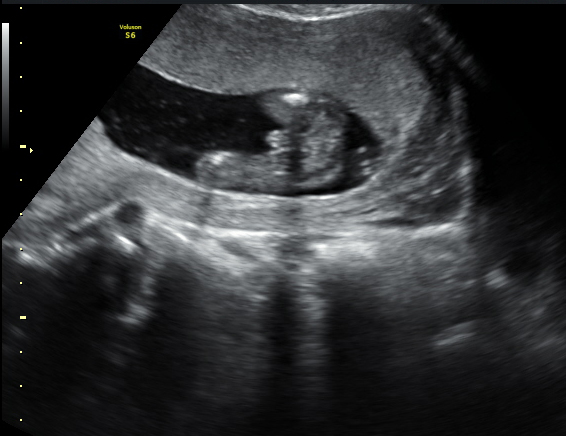

I have attached two images here from my current pregnancy. The side view is from my NT scan at 11.5 weeks. If i am correct, the nub is pointing upwards which means boy. In the second image, it is a potty shot from 16.5 weeks and there is a definite protrusion. So i am unsure why she won't confirm boy at this point. I can't see it being anything else. Am i just better at seeing things than my doc? Can anyone help?